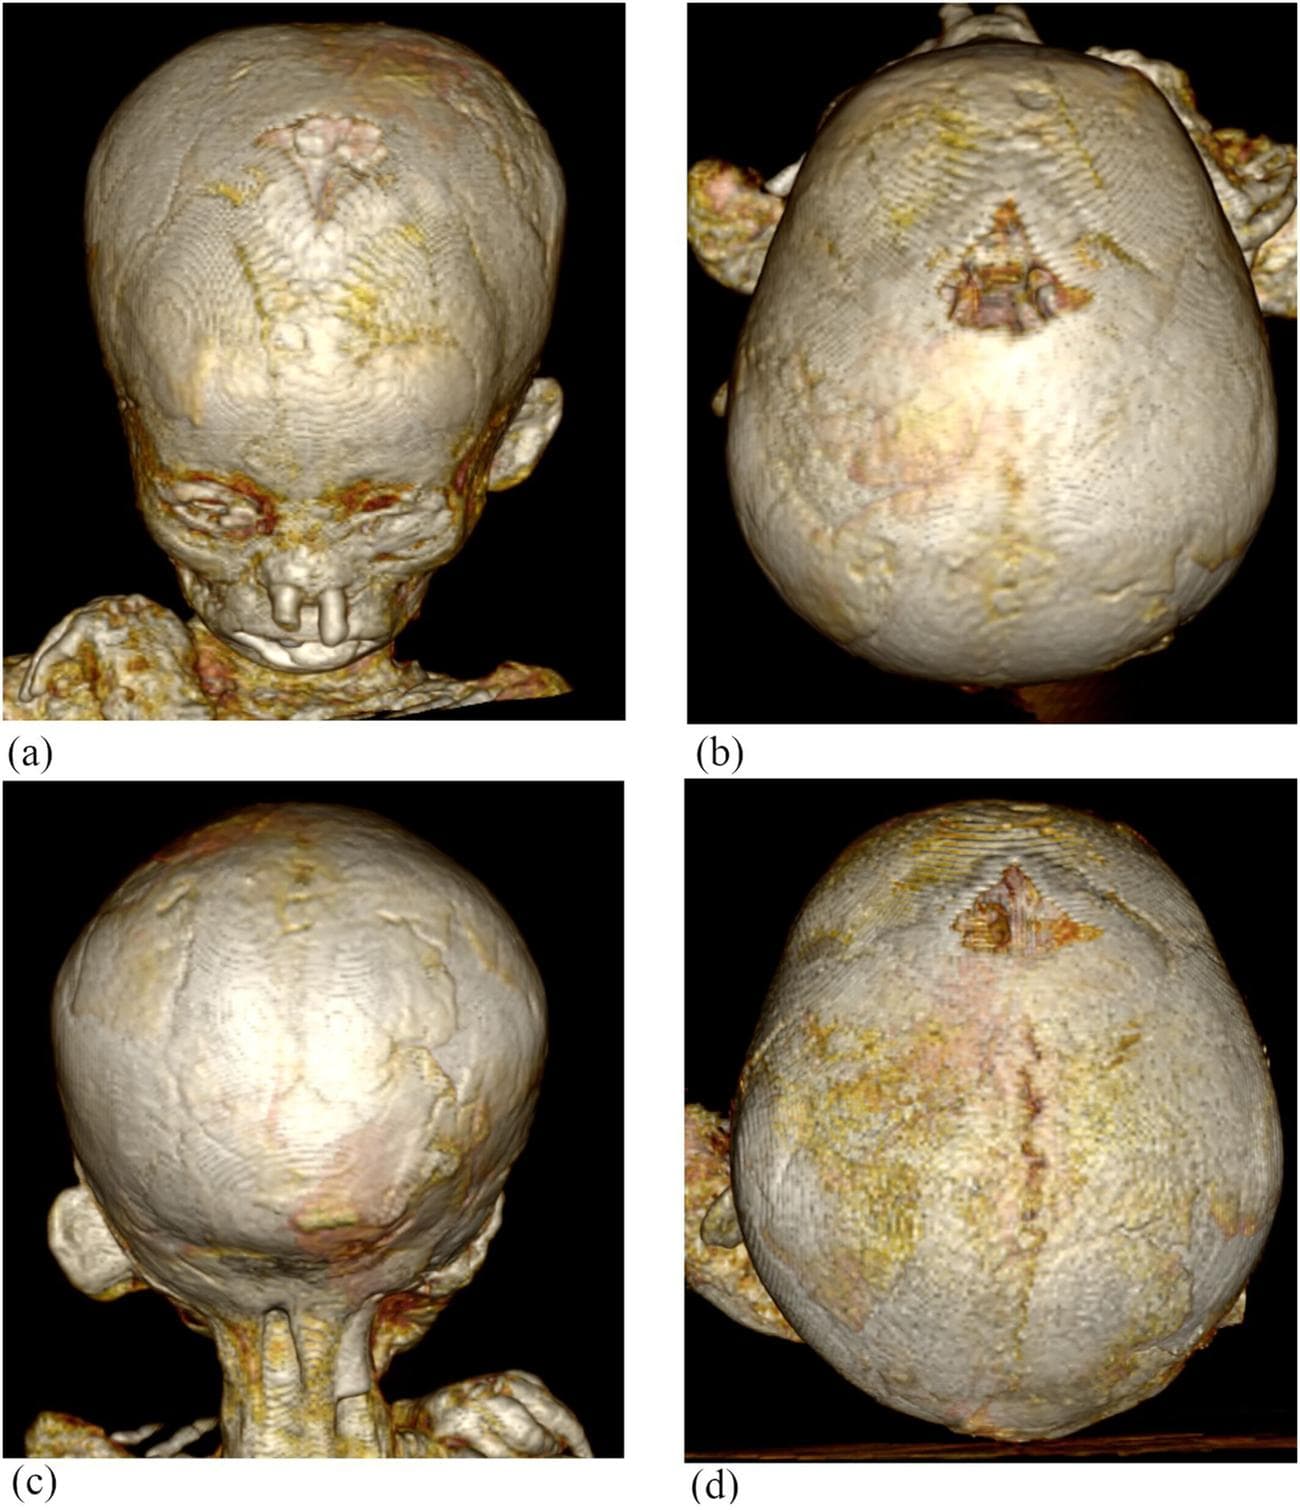

Μία διεθνής ομάδα ερευνητών μελέτησαν τις μούμιες παιδιών από την αρχαία Αίγυπτο, χρησιμοποιώντας αξονικές τομογραφίες και αποκάλυψαν πως μία συγκεκριμένη ασθένεια ήταν αρκετά κοινή εκείνη την εποχή. Μελετώντας μούμιες παιδιών από διάφορα μουσεία της Ευρώπης, διαπίστωσαν πως το 1/3 αυτών έπασχε από αναιμία.

Η μελέτη μας είναι η πρώτη που παραδίδει ραδιολογικά δεδομένα όχι μόνο από το κρανίο αλλά και από τα οστά του προσώπου.

Η χρόνια αιμολυτική αναιμία και η αναιμία από έλλειψη σιδήρου συνήθως συνοδεύονται από μία μεγέθυνση της περιοχής του κρανίου που στεγάζει τον εγκέφαλο, ενώ υπάρχουν και δείκτες όπως αλλαγές στο σχήμα των οστών.

Η ομάδα βρήκε πως από τις 21 μούμιες παιδιών από γερμανικά, ιταλικά και ελβετικά μουσεία, οι 7 είχαν μετρήσιμα σημάδια αναιμίας. Οι μούμιες των παιδιών κυμαίνονταν σε ηλικίες από 1 έως 14 ετών όταν πέθαναν, ενώ έζησαν σε διαφορετικές χρονικές περιόδους.

Η χρονολογικά παλαιότερη μούμια φτάνει μέχρι το 2686 π.Χ., ενώ οι περισσότερες αφορούν την Πτολεμαϊκή και Ρωμαϊκή περίοδο από το 332 π.Χ. έως το 395 μ.Χ. Ο σκοπός της έρευνας ήταν να εκτιμήσουμε την επικράτηση της αναιμίας στις αρχαίες αιγυπτιακές μούμιες παιδιών και να προσφέρουμε μετρήσιμα δεδομένα για μελλοντικές μελέτες.